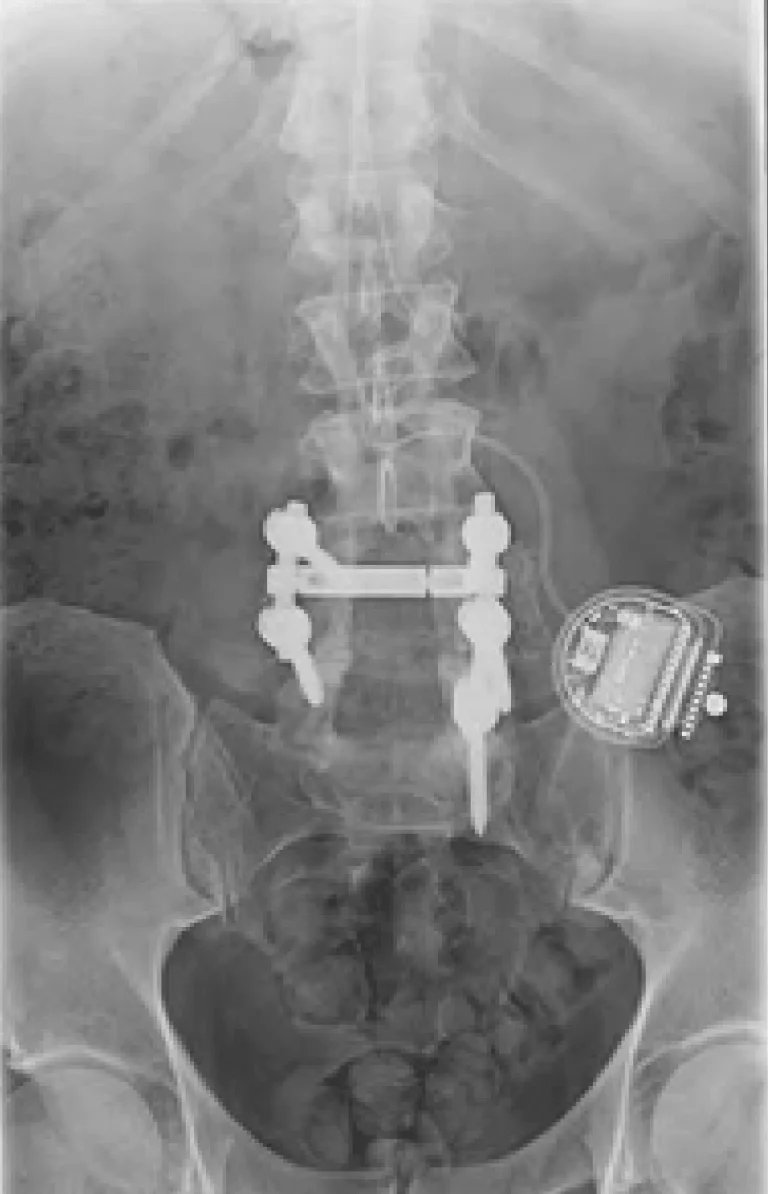

X-ray of a lower spine with metal implants and a medical device on the right side.

Back Pain Gets Worse

Spinal Instability

Laminectomy during placement removes stabilizing structures, causing instability requiring fusion with screws and rods.